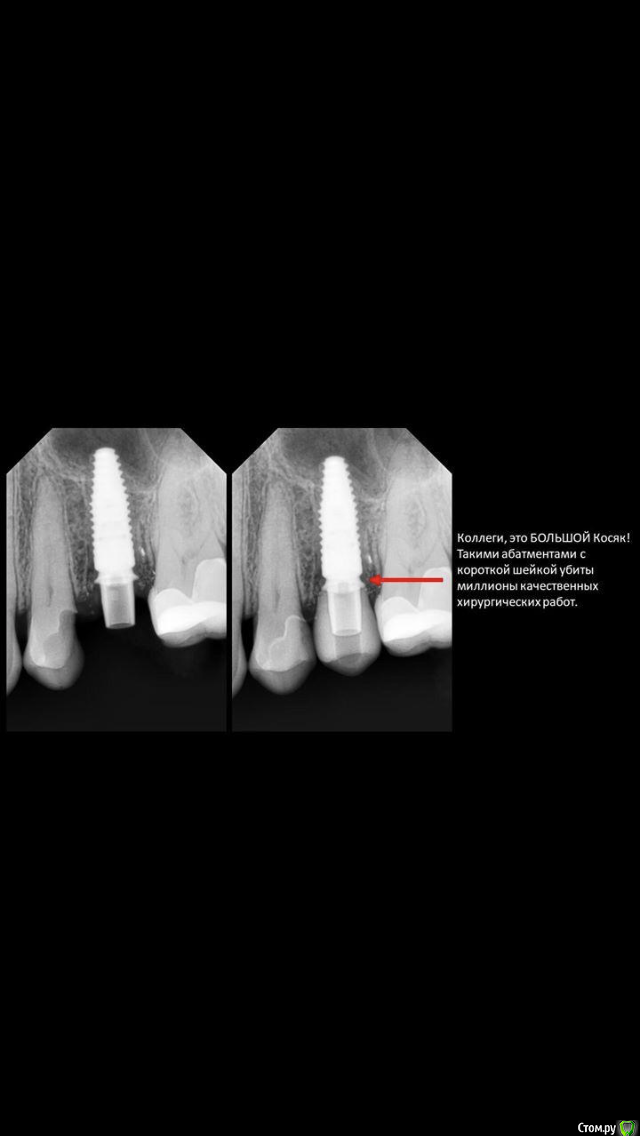

#недозаглубили ....или плюсом десны маловато,вот и при формировании биоширины кость ушла

да нееееет )))) тут как раз наоборот, хирург все норм сделал, а кость ушла от неправильных абатментов.

тот самый случай, когда абатмент с короткой шейкой убил хорошую хирургическую работу